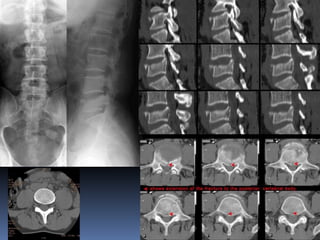

Lumbar myelogram (AP, Lateral & both oblique

views)

1 = conus medullaris 2 = Cauda equina 3 = Left S1

nerve root 4 = Osteophyte

5 = epidural compression due to herniated L4-5 disk

7= Root sleeve

1 7 Lumbar myelogram (AP,Lateral & both oblique views) 1 = conus medullaris 2 = Cauda equina 3 = Left S1 nerve root 4 = Osteophyte 5 = epidural compression due to herniated L4-5 disk 7= Root sleeve